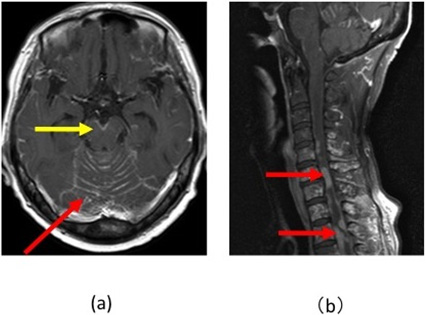

• 脳腫瘍:脳腫瘍の微妙な兆候としては、持続的な頭痛、原因不明の発作、視力の変化、認知および行動の変化などが挙げられます。

• ステージ 4:がんが肝臓や肺などの離れた臓器に転移しています。